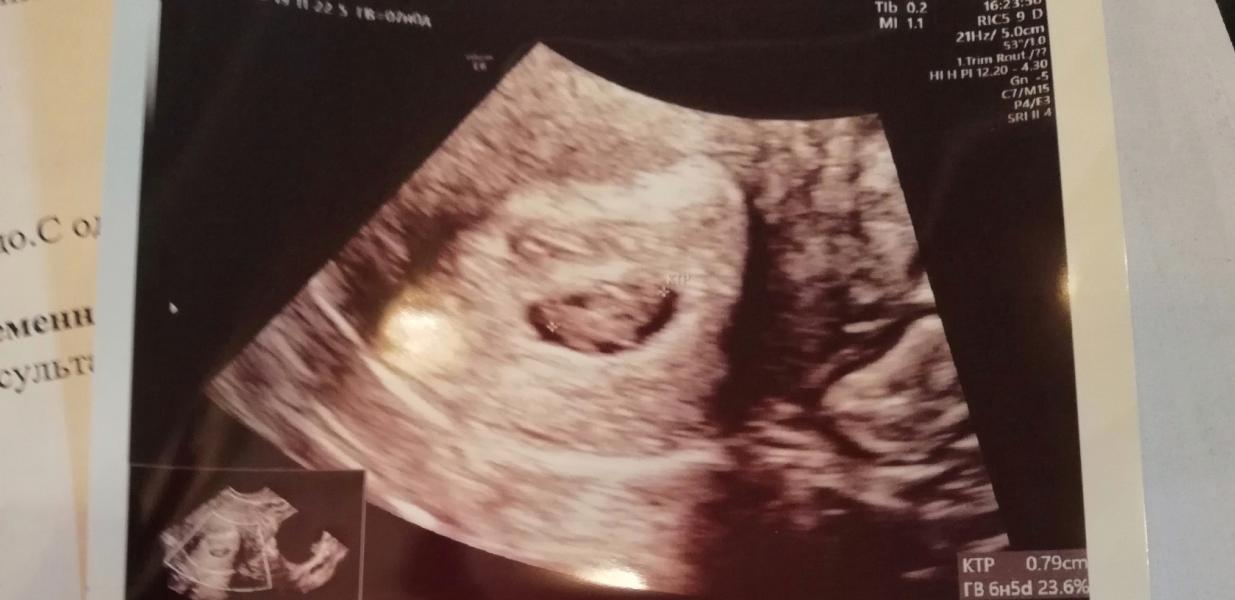

Девочки, сходила на первое узи! Сердечко видно и слышно. Растем)малыш соответствует сроку полностью. Всего 7,9 мм 😁только не сказали где прикрепился хорион, у вас было такое?